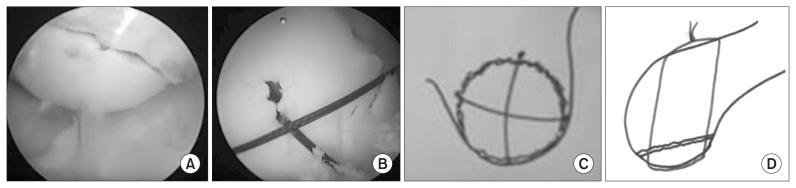

We describe for the first time a case of lateral femoral condyle fracture following a fall in a 13-year-old child that was reduced arthroscopically using a probe. It was definitively fixed with 0 vicryl sutures in a cruciate pattern after being initially stabilised with 1.5-mm Kirschner wires. Four beath pins carrying sutures were drilled at four opposing quadrants through the reduced fragment into the femur. The sutures were then tied on the lateral cortex of the femur. After fixation, the child was kept non-weight bearing for 6 weeks, partial weight bearing from 6 weeks to 12 weeks and then full weight bearing thereafter. Range of motion (ROM) exercises were commenced on the first postoperative day. At one-year follow-up, the ROM was from -5° to 130°, all symptoms disappeared, and complete resumption of all sports activities was allowed.

我们首次描述了一名13岁儿童跌倒后发生外侧股骨髁骨折的病例,该骨折通过关节镜使用探针进行复位。在最初用1.5毫米克氏针稳定后,以十字形用0号薇乔缝线进行确切固定。在复位后的骨折块的四个相对象限,穿过股骨钻四个带缝线的带线针。然后将缝线系在股骨外侧皮质上。固定后,患儿6周不负重,6周至12周部分负重,之后完全负重。术后第一天开始进行活动度(ROM)锻炼。随访一年时,活动度为-5°至130°,所有症状消失,允许完全恢复所有体育活动。